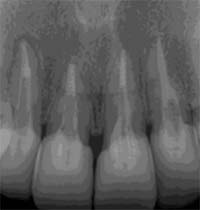

CT撮影で根の状態を“立体的”に診断

レントゲンは2Dですが、CT(3D)では病変の広がり・分岐・湾曲・破折線を正確に把握できます。